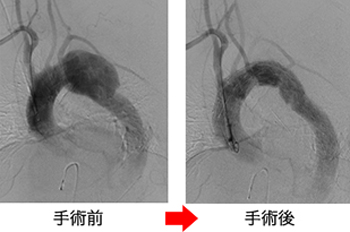

脾動脈瘤に対するコイル塞栓術

動脈瘤にカテーテルでコイル(らせん状の金属)を詰め、血流をなくす。